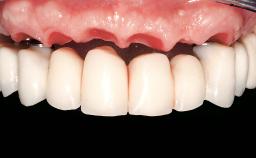

Immediate Loading of Eight Implants in the Maxilla and Six Implants in the Mandible and Final Restoration with Three-Unit and Four-Unit FDPs

Prosthesis Type FDP

SAC Level Complex

Defining Characteristics Fully edentulous upper jaw to be rehabilitated with an implant-borne fixed dental prosthesis

Loading Protocol Immediate